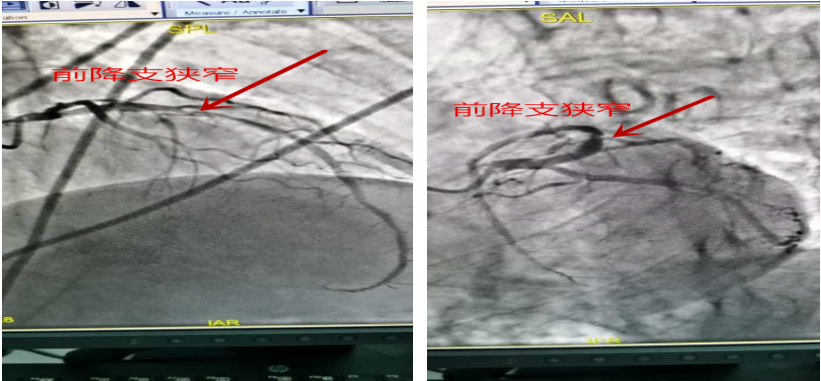

患者杨某某,男,66岁,农民,于2020年03月22日11:40因“发作性胸痛7天”入院。患者于入院前7天(16日10时左右)在劳动时出现胸痛不适,主要为左侧胸部钝痛不适,感轻微压榨感,向背部、左肩及左臂内侧放射,伴心悸不适,持续时间约10-15分钟,患者休息后逐渐缓解;20日7时左右患者再发胸痛一次,与16日相似,但持续时间延长,约30分钟,同日再行发作一次;患者院外未行正规诊治,现无明确胸痛不适。入院后考虑急性非ST抬高 心肌梗死,择期行PCI治疗。患者于2020.03.24 11时在导管室行PCI治疗,手术约50分钟,成功行球囊扩张和支架植入,患者平安返回病房,胸痛缓解。

术前造影:患者前降支近段长病变,最重狭窄约85%。

术后效果: